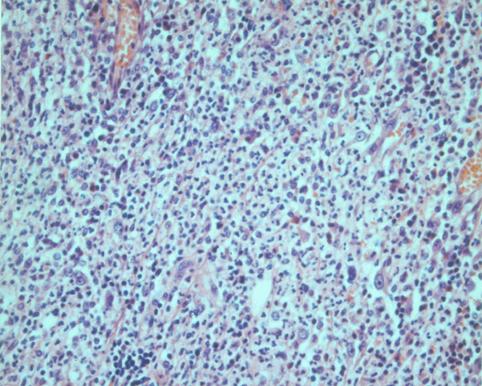

Apendicitis Flegmonosa acompañado de litiasis (Caso presentado por el Centro de Tratamiento Médico Hospital Nacional de Nagasaki)

[Image-ID:2984]

Enfermedad Inflamatoria - Ulcerativa/otros

colon/apéndice cecal

Micro